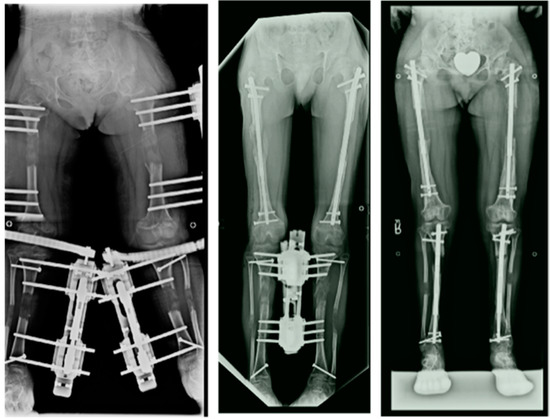

Extensive Limb Lengthening for Achondroplasia and Hypochondroplasia

by Dror Paley

Children 2021, 8(7), 540; https://doi.org/10.3390/children8070540 - 24 Jun 2021

Extensive limb lengthening (ELL) was completed in 75 patients: 66 achondroplasia and 9 hypochondroplasia. The average lengthening was 27 cm for achondroplasia (12–40 cm) and 17 cm for hypochondroplasia (range 10–25 cm). There were 48 females and 27 males. Lengthening was done either [...] Read more.

Extensive limb lengthening (ELL) was completed in 75 patients: 66 achondroplasia and 9 hypochondroplasia. The average lengthening was 27 cm for achondroplasia (12–40 cm) and 17 cm for hypochondroplasia (range 10–25 cm). There were 48 females and 27 males. Lengthening was done either by 2-segment (14 patients; both tibias and/or both femurs) or by 4-segment lengthenings (64 patients; both femurs and tibias at the same time). Most patients also had bilateral humeral lengthening. Patients had 2 or 3 lower limb lengthenings and one humeral lengthening. Lengthenings were either juvenile-onset (31), adolescent-onset (38) or adult-onset (6). The average age at final follow-up was 26 years old (range 17–43 years). There were few permanent sequelae of complications. The most serious was one paraparesis. All patients returned to activities of normal living and only one was made worse by the surgery (paraparesis). This is the first study to show that ELL can lead to an increase of height into the normal height range. Previous studies showed mean increases of height of up to 20 cm, while this study consistently showed an average increase of 30 cm (range 15–40 cm) for juvenile-onset and mean increase of 26 cm (range 15–30 cm) for adolescent-onset. This results in low normal height at skeletal maturity for males and females. The adult-onset had a mean increase of 16.8 (range 12–22 cm). This long-term follow-up study shows that ELL can be done safely even with large lengthenings and that 4-segment lengthening may offer advantages over 2-segment lengthening. While all but the more recent cases were performed using external fixation, implantable limb lengthening promises to be an excellent alternative and perhaps an improvement. Full article